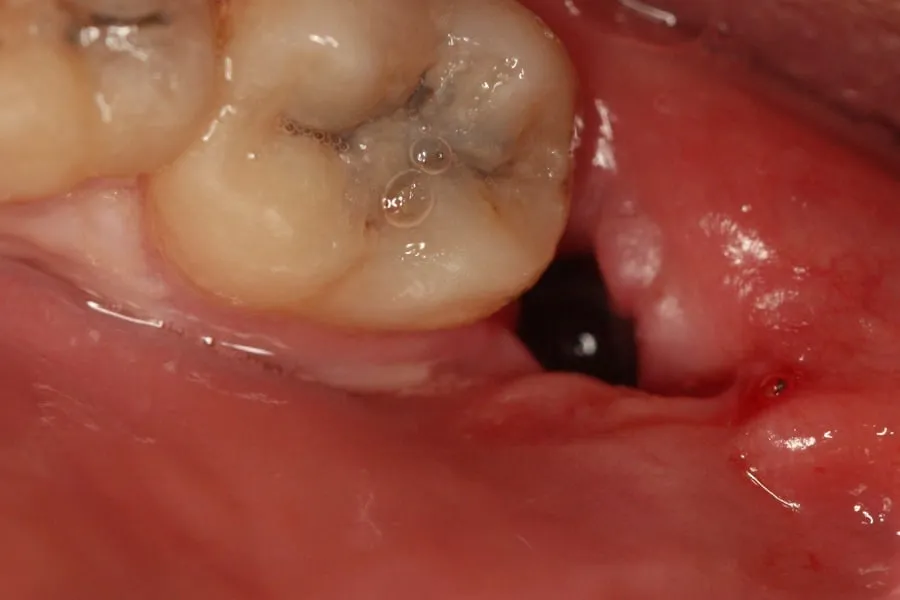

Kiedy opuszczasz gabinet po ekstrakcji zęba, w miejscu usuniętego zęba zastajesz zębodół. To naturalne zagłębienie, które bardzo szybko wypełnia się krwią, tworząc skrzep. Ten skrzep jest ciemnoczerwony, o konsystencji galaretki i powinien wypełniać całą lożę po zębie. Dziąsło wokół rany może być lekko obrzęknięte i zaczerwienione. To zupełnie normalna reakcja organizmu na uraz i początek procesu gojenia. Może też wystąpić niewielkie sączenie krwi, co również nie jest powodem do niepokoju, o ile nie jest to intensywne krwawienie.

Pierwsze 24-48 godzin: Faza zapalna i formowanie się "ochronnego korka"

W tym okresie skrzep krwi w zębodole stabilizuje się i może stać się ciemniejszy, niemal brunatny niektórzy pacjenci opisują go jako wyglądający na "brudny", ale to całkowicie naturalne. Ból i obrzęk są zazwyczaj najbardziej intensywne w ciągu pierwszych 24-48 godzin, po czym powinny stopniowo maleć. Niewielkie sączenie krwi, czyli delikatne krwawienie, jest wciąż normalne i nie powinno budzić niepokoju. Właśnie w tej fazie kluczowe jest, aby skrzep pozostał nienaruszony, chroniąc głębsze struktury.

Dni 3-7: Najważniejszy etap, który często budzi niepokój

To właśnie ten okres często staje się źródłem niepokoju dla moich pacjentów. Pomiędzy 3. a 7. dniem na powierzchni skrzepu może pojawić się białawy lub żółtawy nalot. Bardzo często jest on mylony z ropą, ale w zdecydowanej większości przypadków jest to włóknik (fibryna) naturalny element procesu gojenia, który stanowi rusztowanie dla nowych tkanek. Pod tym nalotem zaczyna tworzyć się ziarnina, czyli nowa, jasnoczerwona lub różowa tkanka. Wygląd rany może wydawać się "nieestetyczny", ale proszę mi wierzyć, jest to prawidłowy i pożądany objaw aktywnej regeneracji.